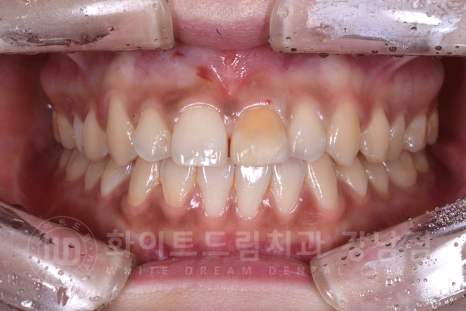

환자분은 이번 앞니 변색을 치료하면서 심미치료를 함께 진행하길 원하셨는데요.

앞니 벌어진 증상과 토끼 앞니도 같이 치료할 수 있나요?

하는 김에 같이 하려구요.

환자분의 구외 사진을 보면 대문니 2개가 유난히 큰 토끼 앞니 양상입니다.

21번 치아를 크라운치료하면서, 11번 치아도 라미네이트를 함께 진행하여 심미적인 부분을 개선하기로 했습니다.

11번 치아 라미네이트와 21번 치아 크라운을 부착하기 전 자연치 상태입니다.

라미네이트는 크라운에 비해서 훨씬 치아 삭제량이 적죠?

21번 치아는 치아 삭제 후 심미성을 위해 레진 코어로 치아 모양을 만들어 놓은 상태입니다.